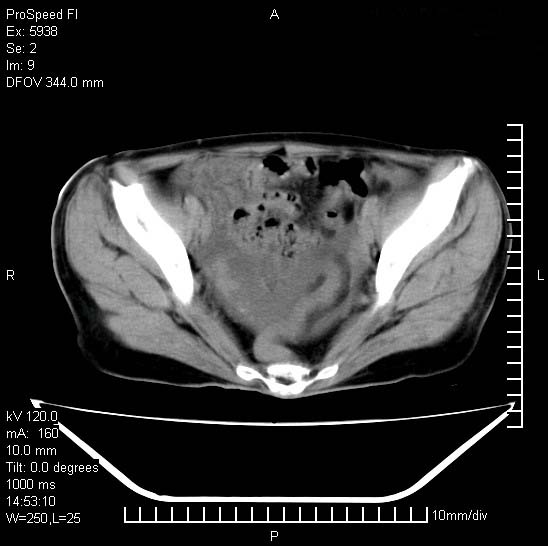

反复小腹疼痛,盆腔积液3年,无发热,曾抗痨一段时间。

右下腹肠管壁增厚,边缘有侵润改变及点状低密度影,内侧可见局限性肿块。考虑-----淋巴瘤或增生型肠结核----盆腔积液-----建议肠镜检查

考虑盆腔及右下腹感染性病变(结核可能)。

结核性腹膜炎伴积液。右侧髂骨骨窗看看,是否有骨质破坏。

提示结核性腹膜炎合并盆腔积液。建议查ppd或tb抗体。